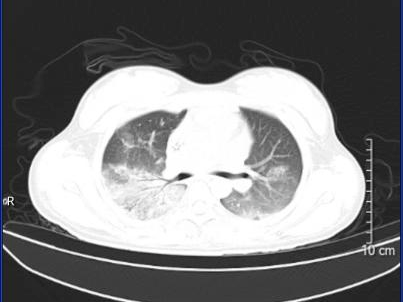

案例2:

58岁阿伯出现咳嗽、咽痛、鼻塞、流涕、头痛,伴有肌肉酸痛,这些症状让阿伯误以为是流感,自行服药后感觉症状加重,甚至出现了呼吸困难。

入院后肺部CT检查结果竟与前几天那名孕妈的如出一辙,同样也是半个肺“全白了”。这让ICU医生警惕起来,迅速考虑到“鹦鹉热”可能,很快便明确了罪魁祸首——“鹦鹉热衣原体”。经过针对性治疗,阿伯的肺部情况明显好转,但由于出现了肝、肾、心等多器官功能损伤,阿伯仍需在ICU接受治疗。

图片

治疗前

治疗后